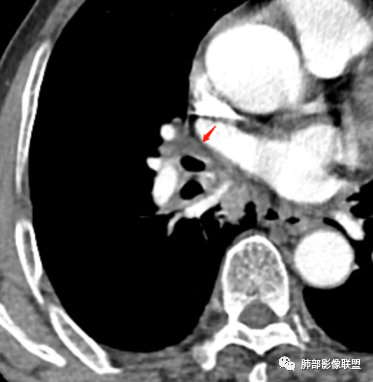

边缘偏平直,内部血管走形自然,一般提示包绕为主。

支气管的堵塞也是让我觉得奇怪,当然这种最终支气管镜很直接。

南边:我是看到血管的改变,病灶的边缘,支气管还有中叶的树芽,倾向于炎性。

(2)支气管和血管:右肺支气管分支管壁弥漫性增厚,中间段支气管散在结节样凸起,右肺下叶内基底段支气管闭塞,但远端可疑复出。余病灶围绕支气管腔内远端无明显阻塞性不张。内部血管走形自然,提示包绕为主。